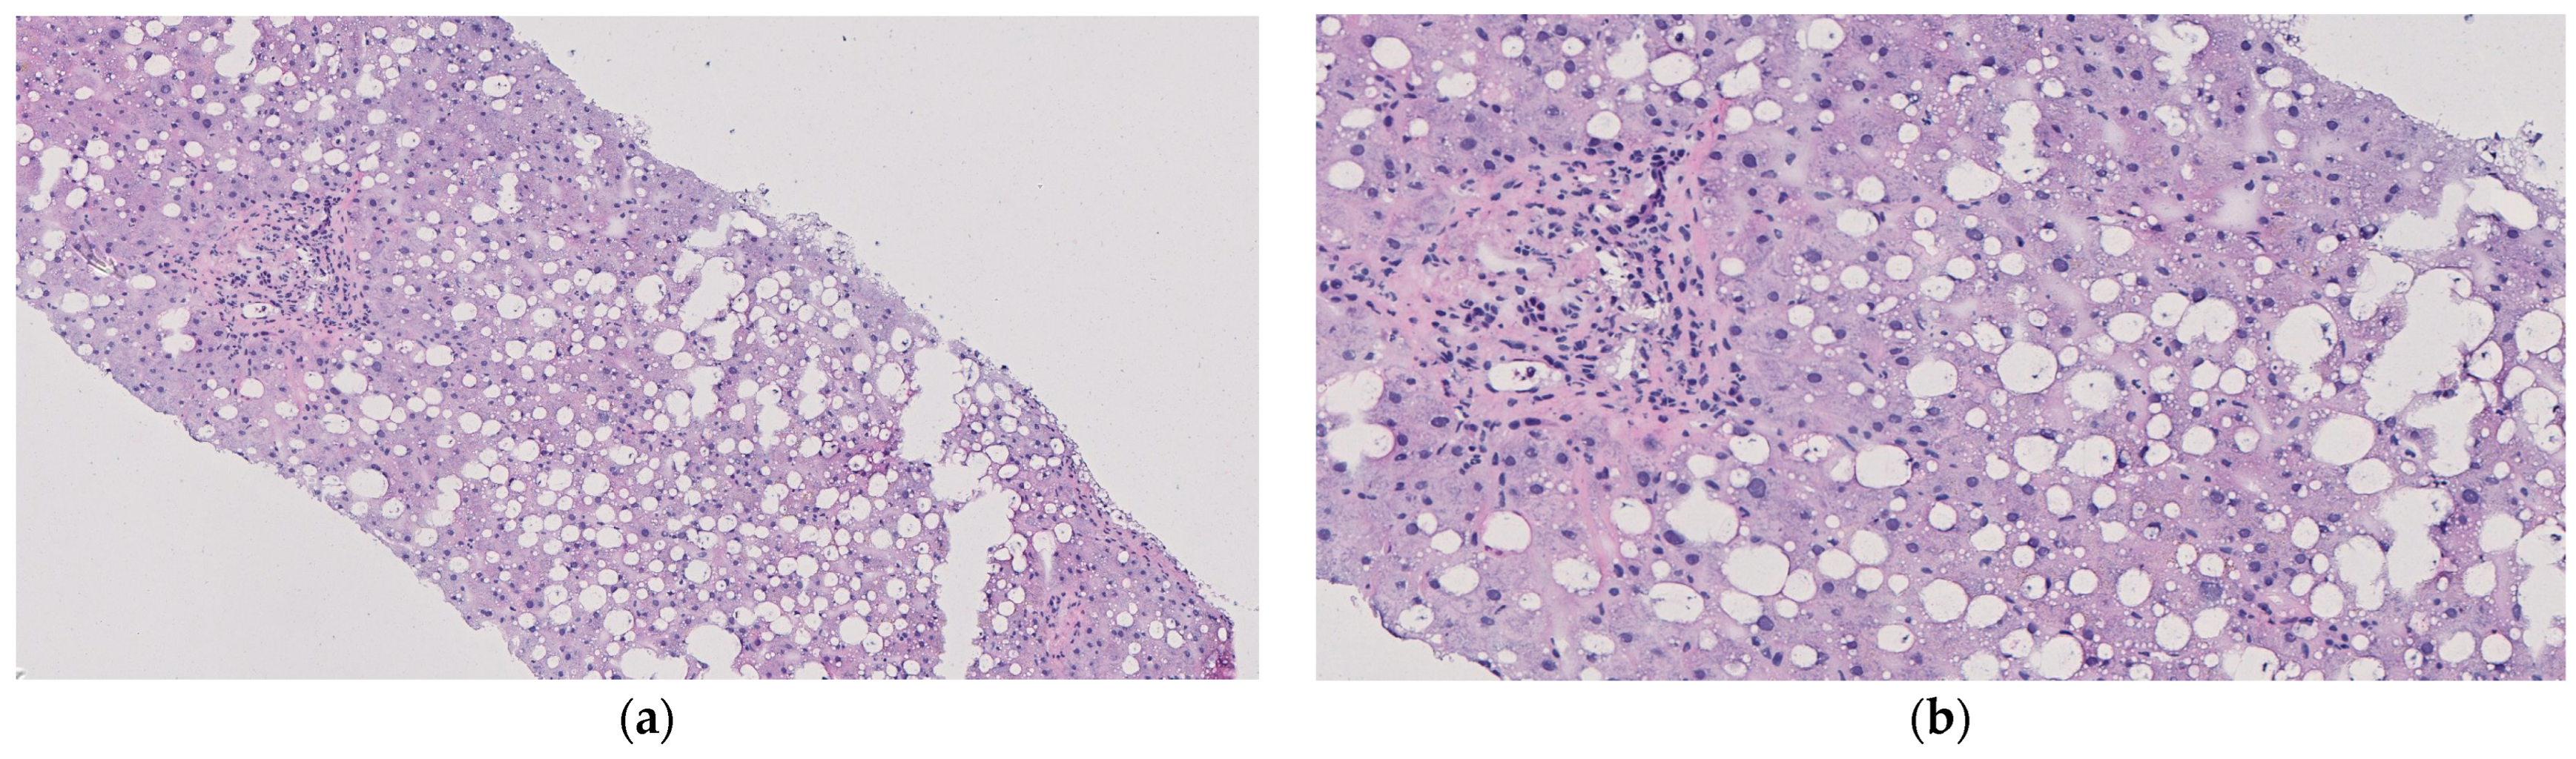

3.1. Procurement

3.2. Primary Perfusion

3.3. Secondary Perfusion